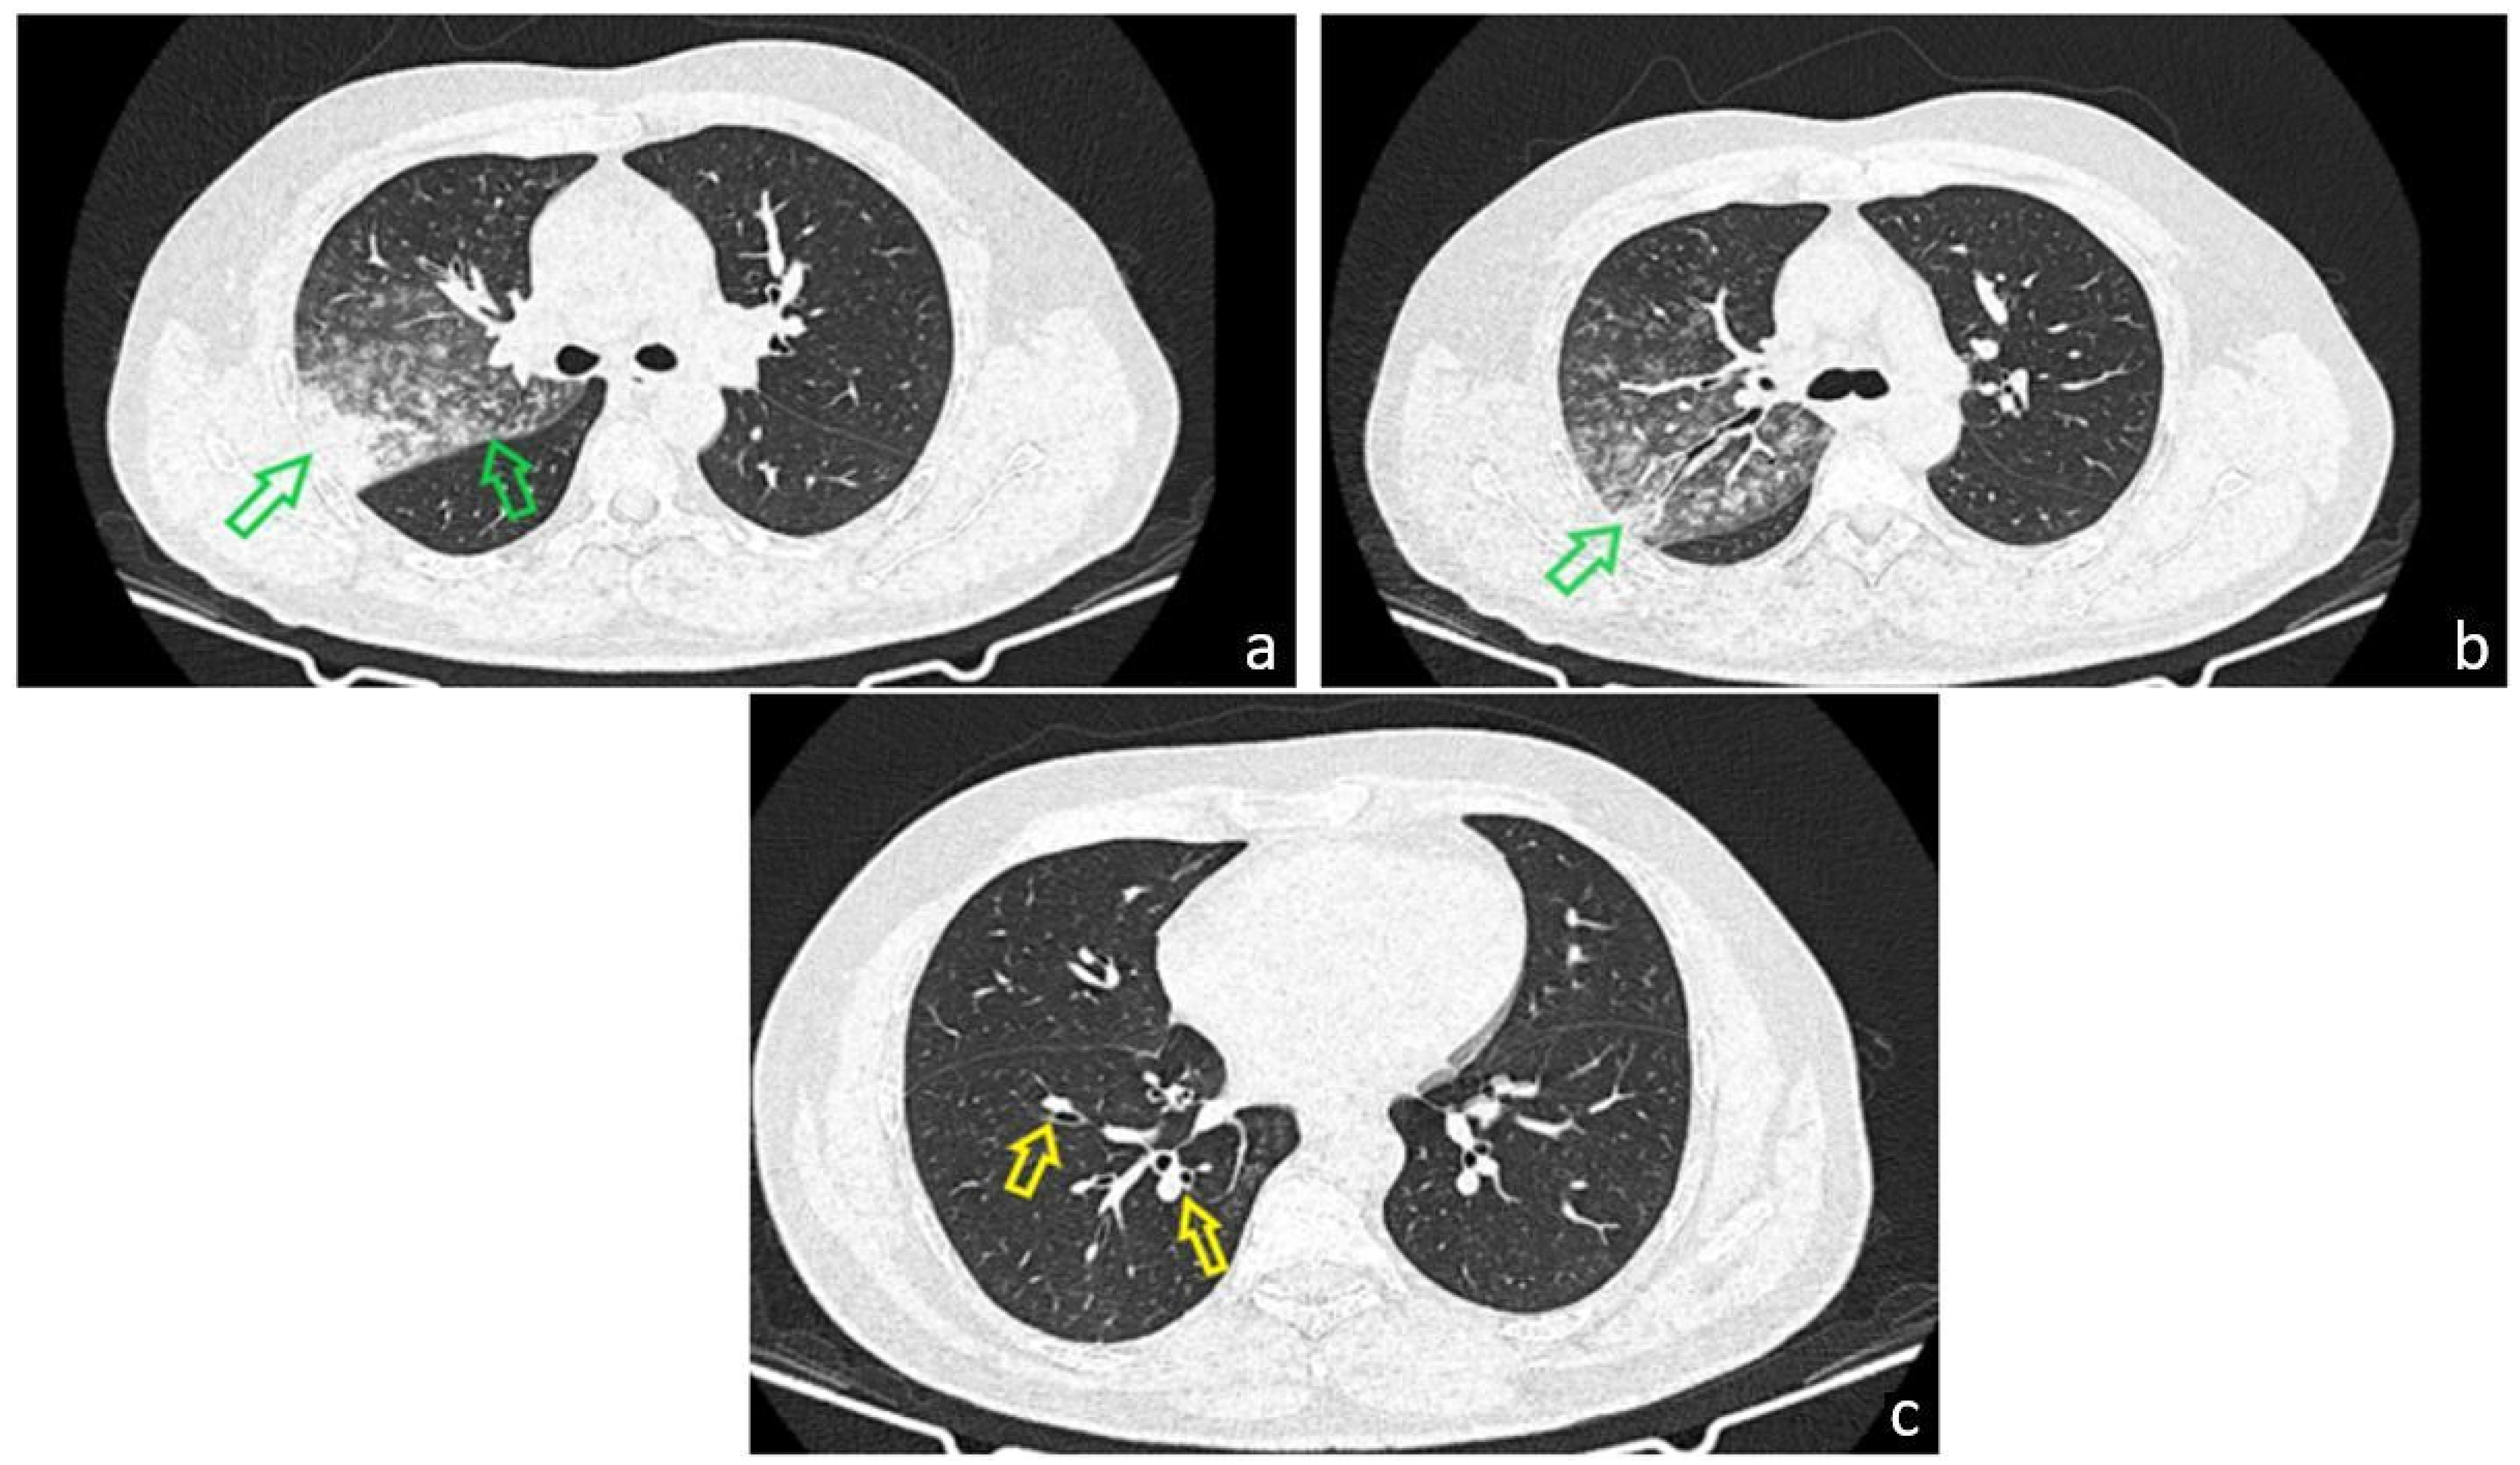

Figure 5. The patient underwent bronchoscopic re-evaluation one month after the initial diagnosis. He was in good general condition, without respiratory symptoms. Follow-up CT imaging demonstrated a favorable evolution, with regression of the pulmonary lesions of infectious appearance (a,b), while persistent cylindrical bronchiectasis was noted in the lower lobes ((c), red arrow). Pulmonary function testing showed improvement in forced vital capacity (FVC) from 66% to 78% of the predicted value, approaching the lower limit of normal. Follow-up fiberoptic bronchoscopy revealed a larynx with preserved dynamics and a mild, diffuse, bilateral congestive appearance. No proliferative elements or active mucosal lesions were detected. A subtle broadening of the bronchial spurs was noted at the intersegmental level of the right upper lobe; otherwise, the mucosa appeared normal. The previously described tracheal lesion was no longer evident, which may reflect a transient immunosuppressive state during pneumonia, leading to reactivation of a latent HPV infection that subsequently regressed as the pulmonary infection resolved. The patient remains under pneumology follow-up, with a scheduled bronchoscopic re-evaluation in three months, given the prior histopathological findings and the immunohistochemical detection of HPV DNA genotype 45. Additionally, the patient was referred to the Gynecology Department for assessment of HPV vaccination eligibility. Although Tracheal tumors represent a diagnostic challenge for clinicians because their symptoms are typically nonspecific and often appear late, with airway obstruction being the most serious and potentially life-threatening manifestation. Most tracheal tumors are malignant, usually arising from direct invasion by adjacent malignancies or via hematogenous dissemination. The often delayed diagnosis significantly narrows the window for potentially curative treatment, such as surgical resection, and contributes to the poor overall 5-year survival rate of approximately 27% [1]. Curative surgery is further limited by the anatomical constraints of the trachea and the extent of tumor invasion. As a result, alternative therapeutic modalities—including chemotherapy, radiotherapy, and advanced bronchoscopic interventions—are more frequently employed for palliation and extension of survival, though none offer a definitive cure. Primary tracheal cancer is rare. In adults, about 90% of primary tracheal neoplasms are malignant, with squamous cell carcinoma and adenoid cystic carcinoma together accounting for over 60% of cases [1]. A wide spectrum of other primary malignant tumors may also arise from the trachea, comprising roughly one-third of cases (≈38.9%) [1]. Reported histologic subtypes include undifferentiated carcinoma, small-cell carcinoma, adenocarcinoma, large-cell carcinoma, melanoma, lymphoma, carcinoid tumors (typical and atypical), and sarcoma. Given the rarity of these tumors, no prospective studies have been conducted; thus, current knowledge about their clinical behavior and optimal management relies largely on case reports and small case series. Risk factors for malignant tracheal tumors differ by histologic type. For squamous cell carcinoma, the strongest associations include tobacco use, alcohol consumption, and a higher prevalence in males. In contrast, adenoid cystic carcinoma shows a more balanced sex distribution and occurs more frequently in non-smokers [1,2]. Dysplasia represents a spectrum of architectural and cytologic abnormalities within the squamous mucosal epithelium and is associated with an increased risk of malignant transformation. Beyond the well-established risk factors of tobacco and alcohol use, gastroesophageal reflux disease has also been implicated, whereas transcriptionally active human papillomavirus (HPV) is generally regarded as playing only a minor role in the pathogenesis of airway dysplasia [3]. This underscores the distinctiveness of our case, in which HPV DNA subtype 45 was identified on immunohistochemical testing of the patient’s tracheal biopsy. We hypothesize that a transient immune imbalance related to pneumonia may have triggered reactivation of a latent HPV infection, thereby contributing to the development of moderate squamous dysplasia of the trachea. This emphasizes the need for clinicians to maintain a broad differential diagnosis and to consider less common etiological factors when evaluating dysplastic airway lesions. Human papillomaviruses (HPVs) comprise over 100 types, with 12 recognized as Group 1 carcinogens—“carcinogenic to humans”—by the International Agency for Research on Cancer (IARC) [4]. Most HPV infections are asymptomatic and spontaneously cleared by the host immune system; however, a subset persists and may, in rare instances, progress to malignancy. Emerging evidence suggests that viral genotype and intra-type genetic variation within high-risk HPVs influence both viral persistence and clinical outcomes. HPV45, a high-risk genotype first identified in 1987 in a woman with recurrent cervical lesions in the United States, belongs to the alpha-7 phylogenetic species, together with HPV18. Like HPV18, HPV45 is more frequently detected in cervical adenocarcinomas than in squamous cell carcinomas. Globally, HPV45 is present in about 5% of cervical cancers, with regional prevalence ranging from 3% in Eastern Asia to 9% in Africa. Based on its enrichment in cervical cancers compared with cytologically normal women, HPV45 is ranked as the third most carcinogenic HPV type, following HPV16 and HPV18 [4]. Genetic variants of HPV45 are currently classified into two major lineages (A and B) and five sublineages (A1, A2, A3, B1, and B2). Lineages differ by approximately 1.0% in whole-genome sequence, while sublineages exhibit 0.5–0.9% nucleotide divergence. Unlike other high-risk HPV types such as HPV16, the relationship between HPV45 genetic variants and cervical cancer risk has not been systematically investigated [4]. Although primary tracheal neoplasms are rare, several HPV-associated tracheal malignancies have been reported. Imai et al. described a 75-year-old man presenting with cough and dyspnea. Chest CT revealed tracheal narrowing caused by an intraluminal mass. Histopathology confirmed papillary squamous cell carcinoma with p16 overexpression, and HPV18 DNA was detected by multiplex PCR. At the 12-month follow-up after adjuvant radiotherapy, the patient showed no local recurrence or distant metastasis [5]. Liu et al. reported a 38-year-old woman with a 16-month history of hemoptysis, chest pain, and intermittent fatigue, initially misdiagnosed with tuberculosis based on a positive interferon-γ release assay. Bronchoscopy revealed tracheal wall congestion and edema with a small lesion on the right lateral tracheal wall. Endoscopic biopsy ultimately confirmed squamous cell carcinoma, and metagenomic next-generation sequencing (mNGS) detected HPV16 DNA in the tumor tissue. Testing of her sexual partner demonstrated HPV16 positivity in penile scrapings, supporting the hypothesis of oral-sexual transmission [6]. Suzuki et al. described a 34-year-old man with dyspnea, in whom CT revealed a 2.0 × 1.6 × 1.0 cm polypoid tumor at the tracheal carina with possible extratracheal extension. Urgent bronchoscopic resection was performed both to establish a diagnosis and to prevent impending airway obstruction. Histopathology showed well-differentiated squamous cell carcinoma, and multiplex PCR identified HPV6 DNA in the resected specimen. Following carinal extraction and reconstruction, the patient remained recurrence-free and without anastomotic complications at 1-year follow-up and did not require adjuvant therapy [7]. HPV45 is a recognized high-risk HPV genotype implicated in several cancers, including cervical, anal, and genital malignancies [4]. Although HPV is an established etiologic factor in oropharyngeal cancers, its specific association with laryngeal and tracheal tumors remains insufficiently defined, largely due to the rarity of primary tracheal malignancies and the limited number of reported HPV-related tracheal cases in the literature. This case highlights the critical role of histopathological assessment of tracheal biopsy specimens, complemented by immunohistochemical testing, in identifying underlying etiologic factors such as HPV infection. Early recognition of such uncommon associations may inform patient management, surveillance strategies, and potential preventive measures, including consideration of HPV vaccination in appropriate populations.